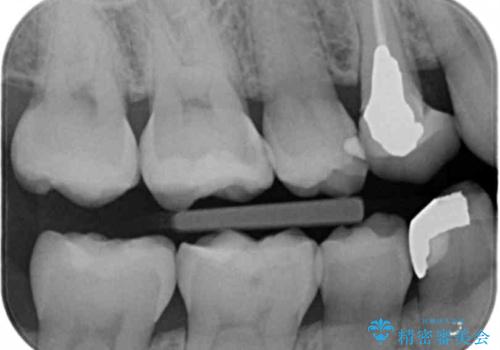

- 銀歯が目立つから白くしたいとのことで来院されました。

当初は元の詰め物と同じインレータイプでの修復予定でしたが、残った歯の厚みが薄く、今後の破折リスクを考慮しクラウンタイプでの修復処置となりました。

残った歯が薄い状態で保存するとその後の破折リスクが高くなります。

予防的に歯を削りクラウンにすることで治療後の破折リスクを減らすことができます。